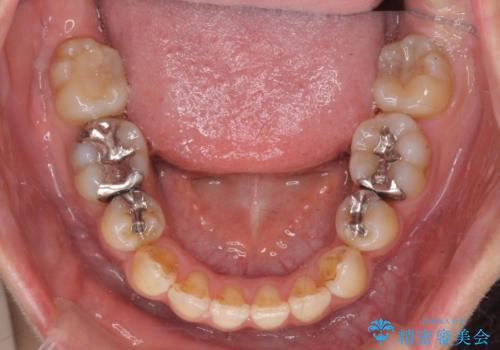

- 八重歯・がたつきのある歯並びの改善を求めて来院されました。

全部の歯が入り切るスペースがなかったため、小臼歯4本を抜去しワイヤーを用いたマルチブラケット矯正を選択しました。